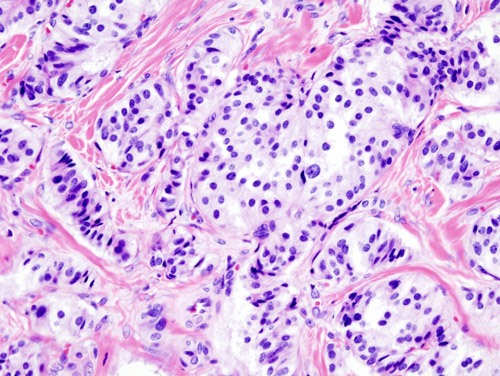

Гистологическое строение инсулиномы